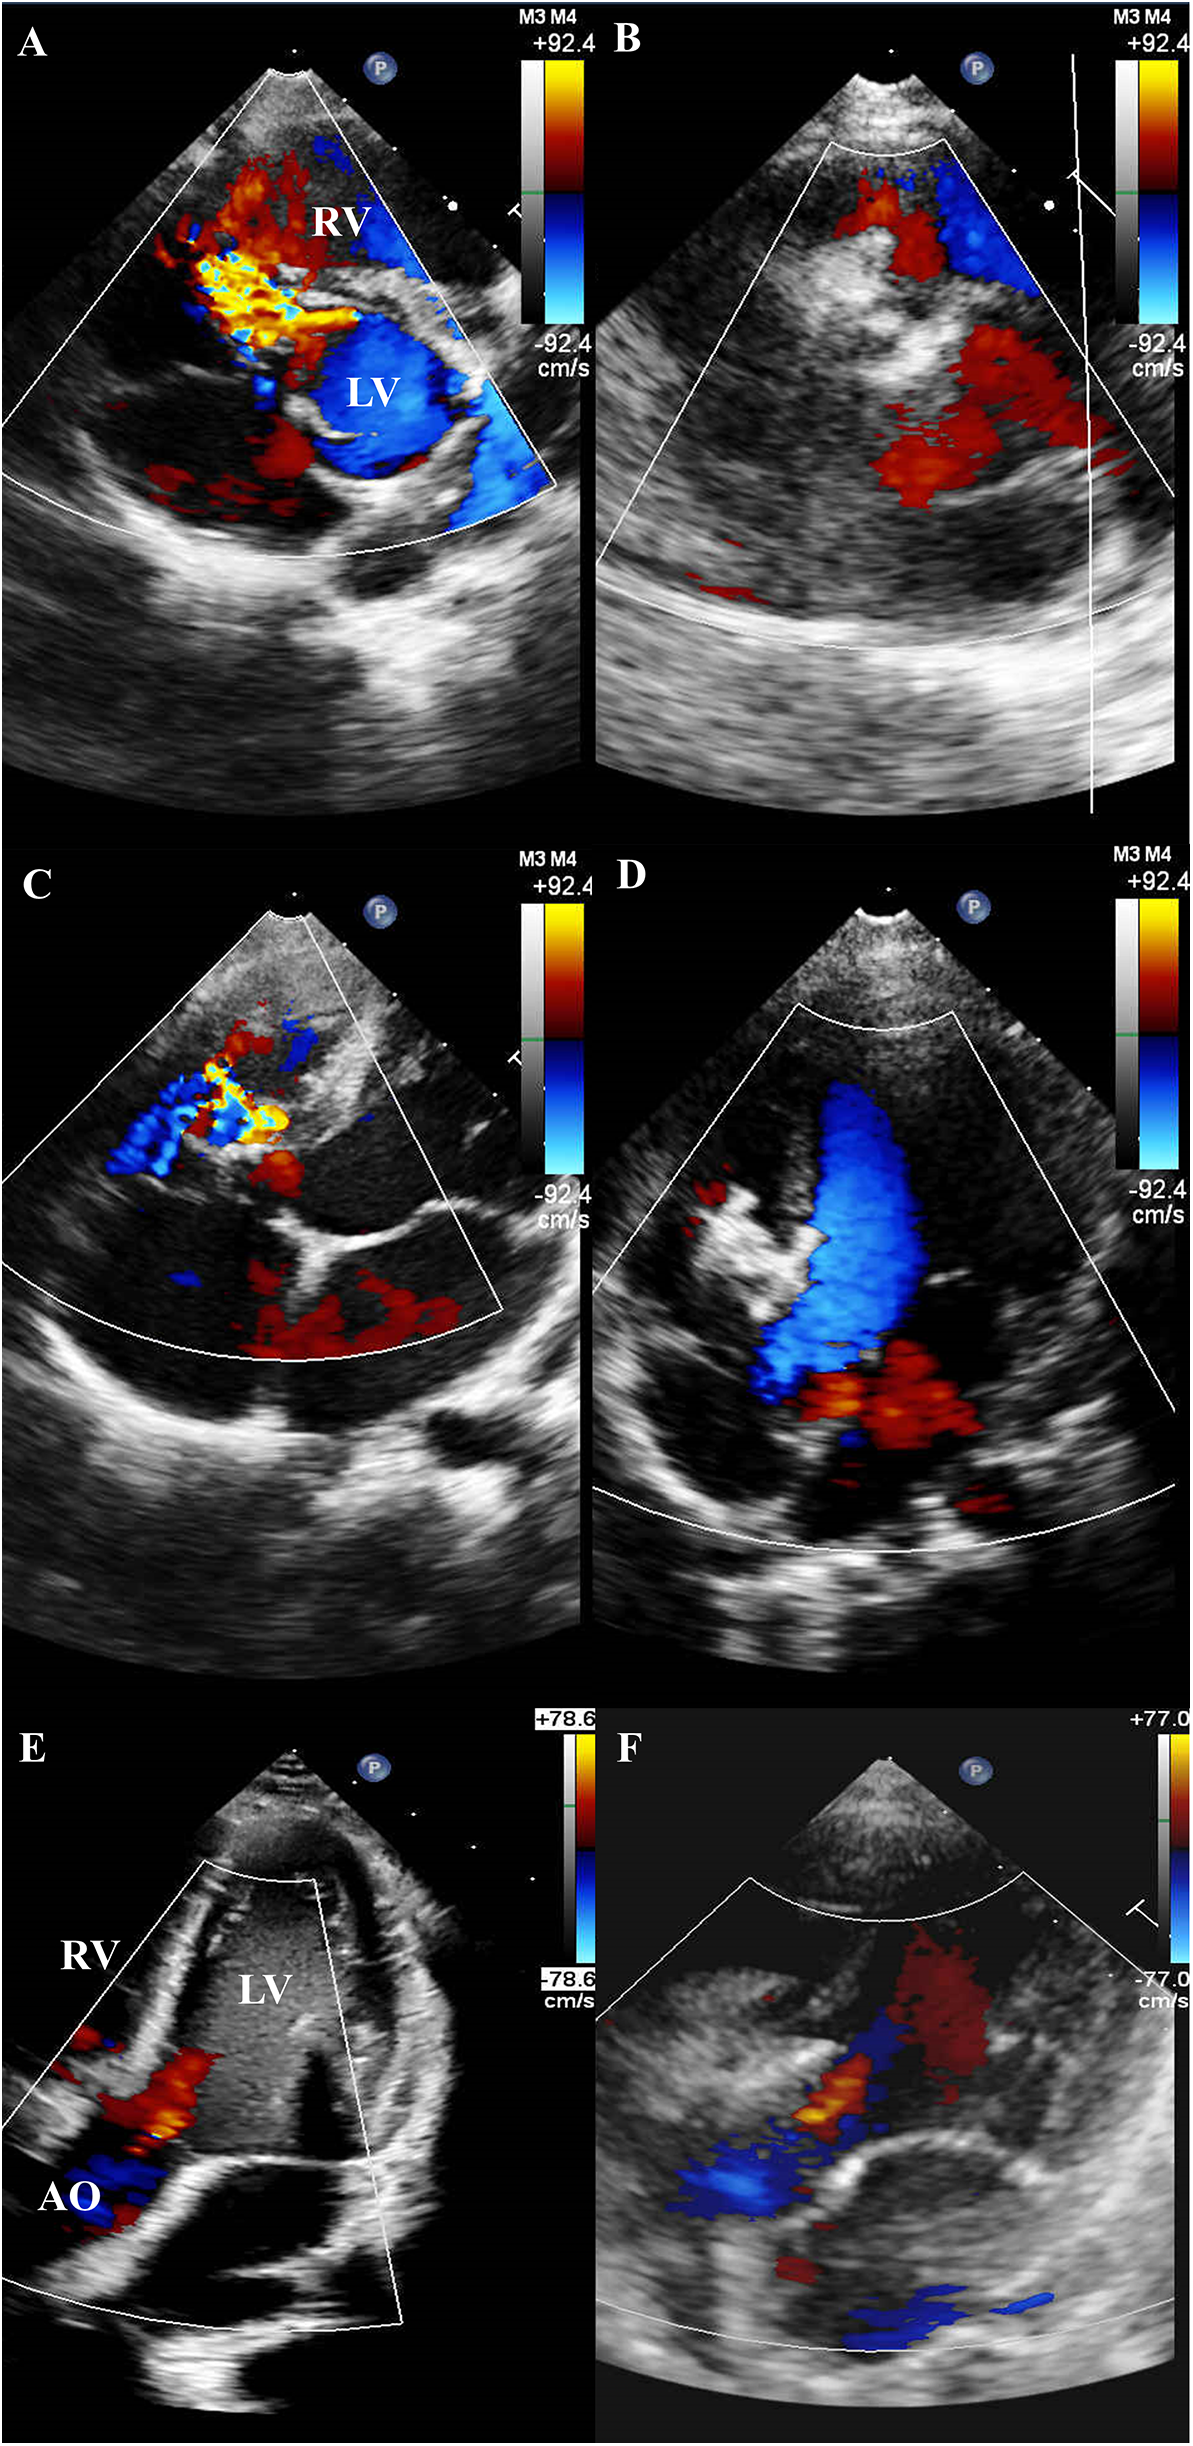

Residual shunts were detected in 57 (49.6%) patients after device deployment—17 trivial, 32 mild, and 8 moderate. Complete closure rates improved progressively over time: 51.3% the next day, 62.6% at 1 month, 69.6% at 3 months, and 83.5% at 6 months. No patient developed progressive AR during follow-up. TTE further illustrated the structural changes before and after intervention. Pre-procedural TTE revealed aneurysmal tissue in the short-axis view (Figure 2A) and mild AR in several cases (Figure 2C). At 6-month follow-up, TTE confirmed complete closure of the defect without residual shunting (Figure 2B), and the degree of AR remained stable in all patients, with no evidence of progression (Figure 2D).

Figure 2

TTE findings before and after device implantation. (A) Pre-procedural TTE (short-axis view) revealing a PmVSD with associated aneurysmal tissue. (B) Follow-up TTE at 6 months (short-axis view) demonstrating complete closure of the PmVSD without residual shunt. (C) Pre-procedural TTE revealing a PmVSD with associated aneurysmal tissue. (D) Follow-up TTE at 6 months demonstrating complete closure of the PmVSD without residual shunt. (E) Pre-procedural TTE demonstrating mild AR. (F) Follow-up TTE at 6 months showing persistent mild AR, with no evidence of progression following device implantation.